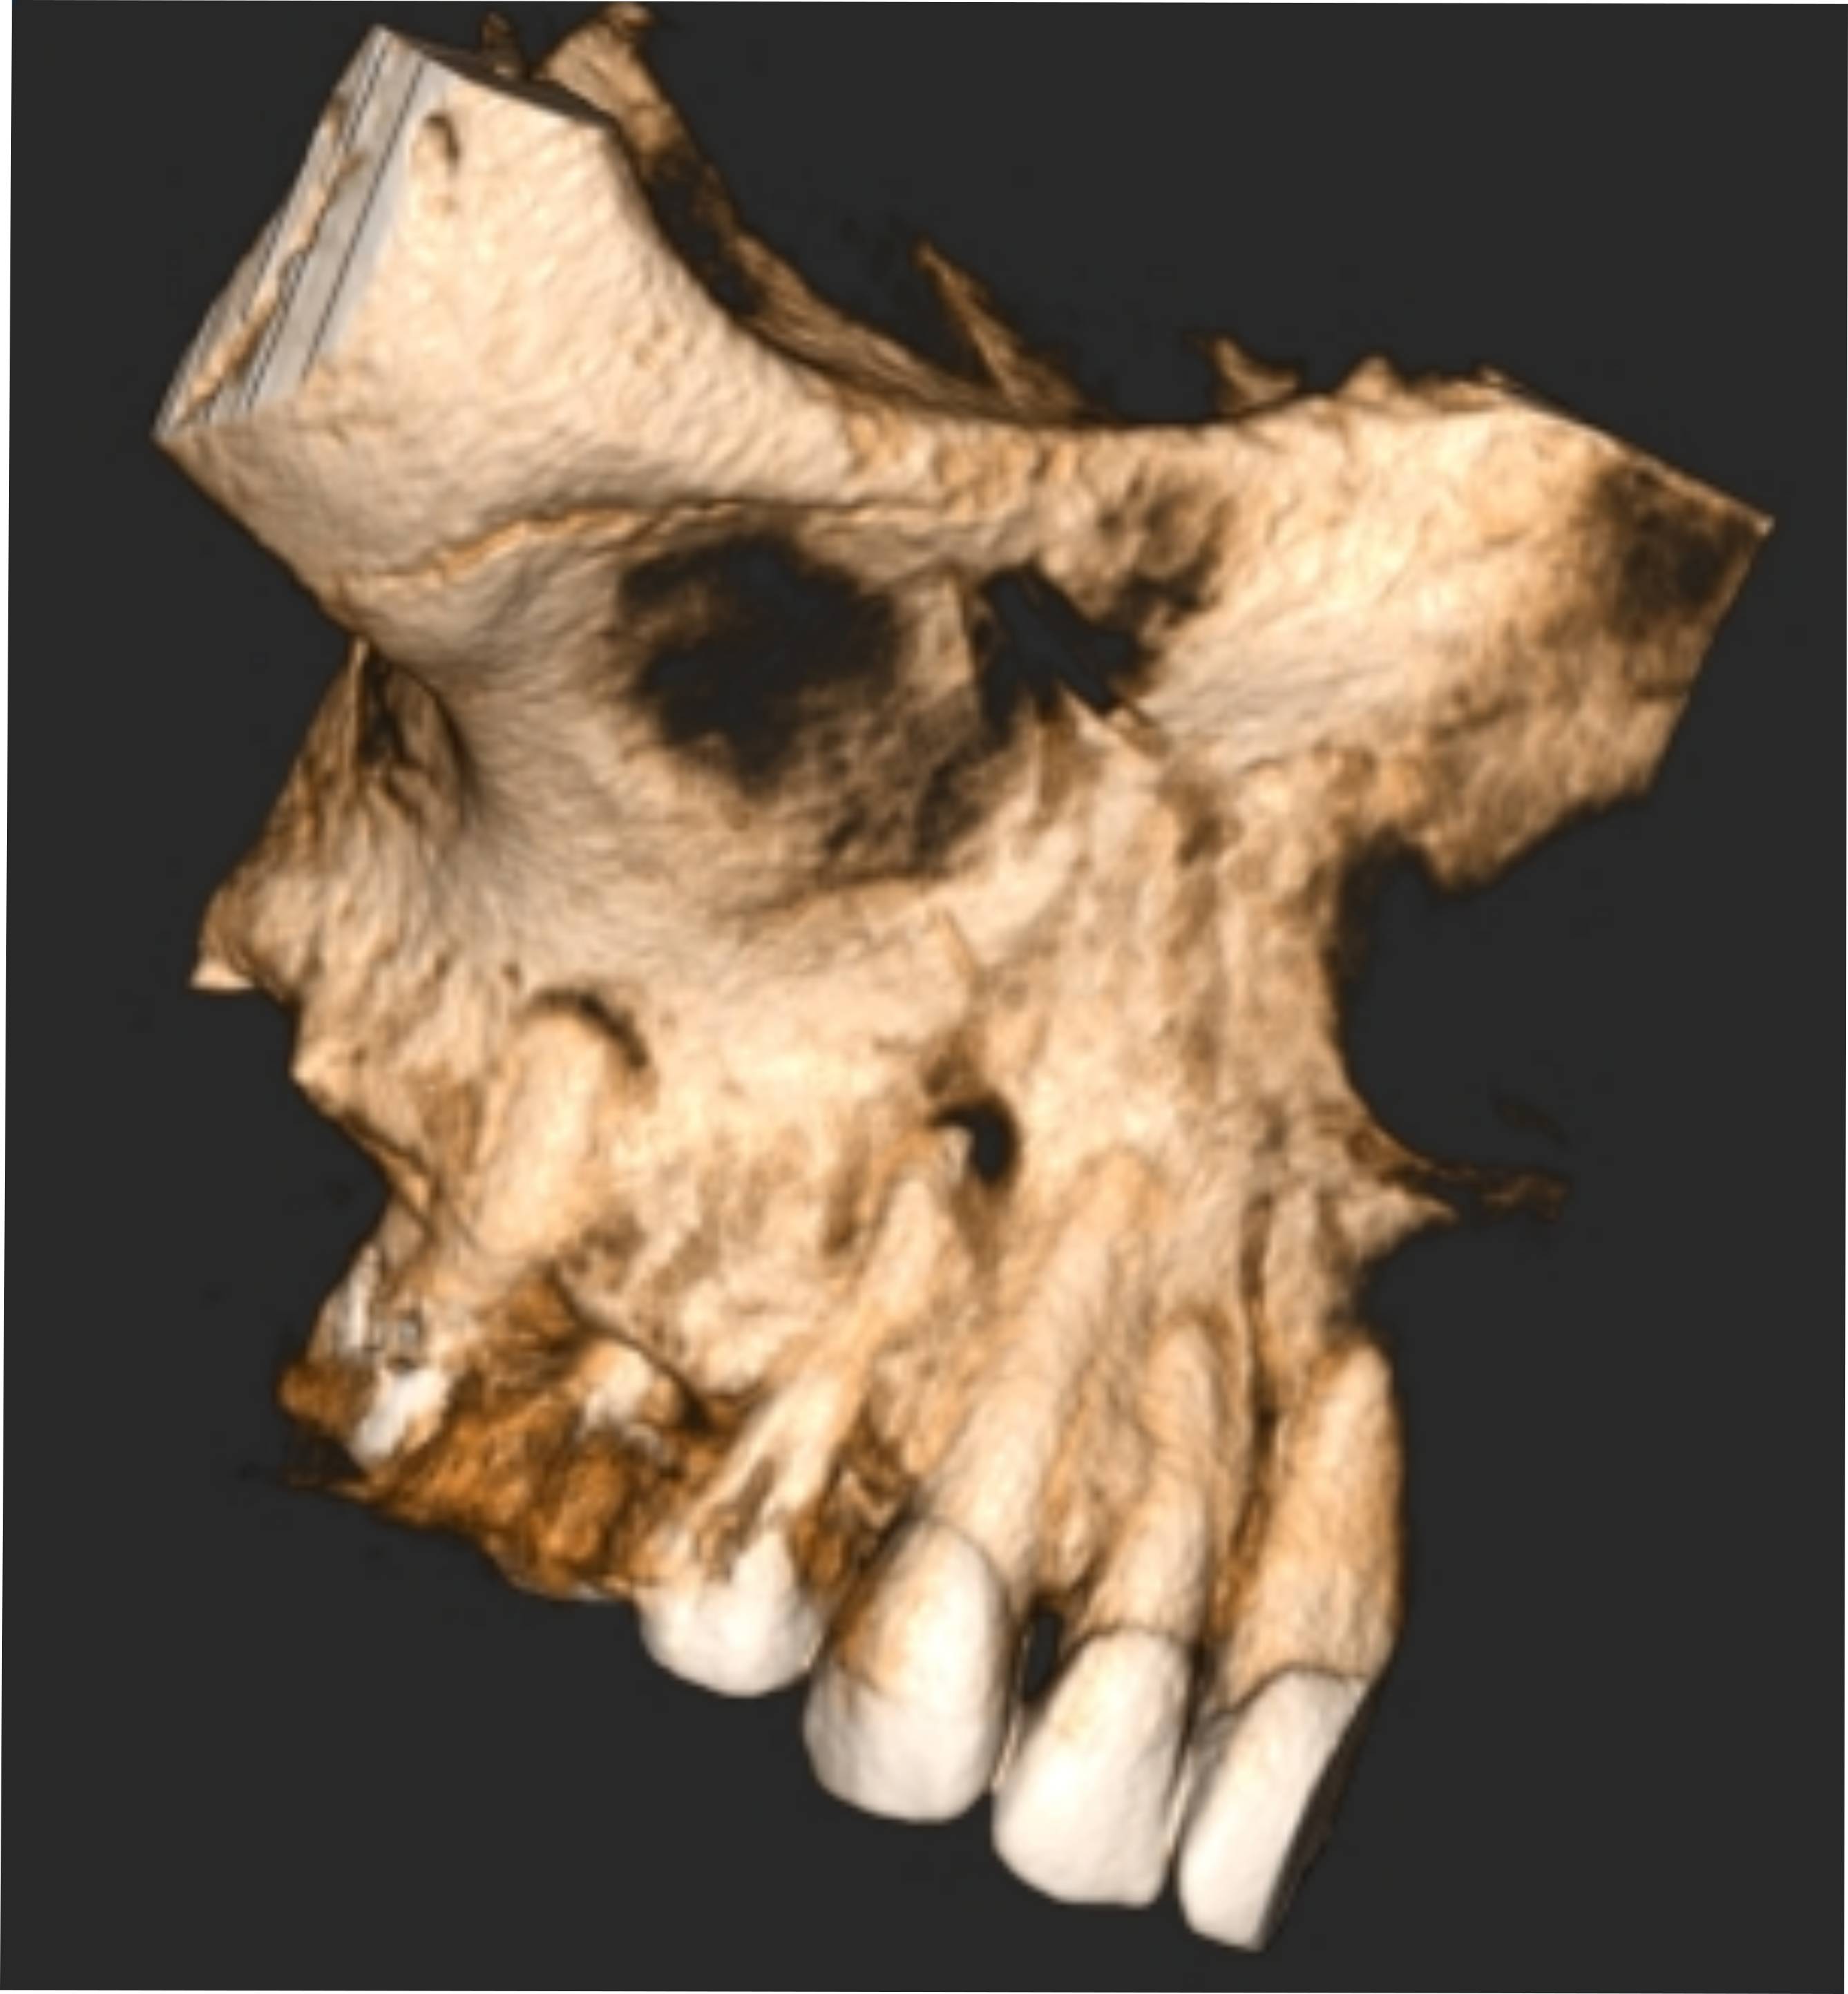

< Volver a "Diagnóstico por Imagen Dental"El examen CBCT es extraordinariamente útil tanto para endodoncistas como para periodoncistas, dado que ofrece imágenes de altísima calidad que permiten identificar todos los detalles de la zona a estudiar, determinar con exactitud la patología y planificar meticulosamente un tratamiento eficaz, así como la antamoía y sus posibles variantes

El objetivo de este estudio es ofrecer la visión más amplia de la pieza a tratar. Se realizan diferentes tipos de cortes, llegando a un grosor mínimo de 0,125mm en todos los planos posibles.

Esta exploración se entrega siempre con el Software NNT gratuito para no perderse el más mínimo detalle.